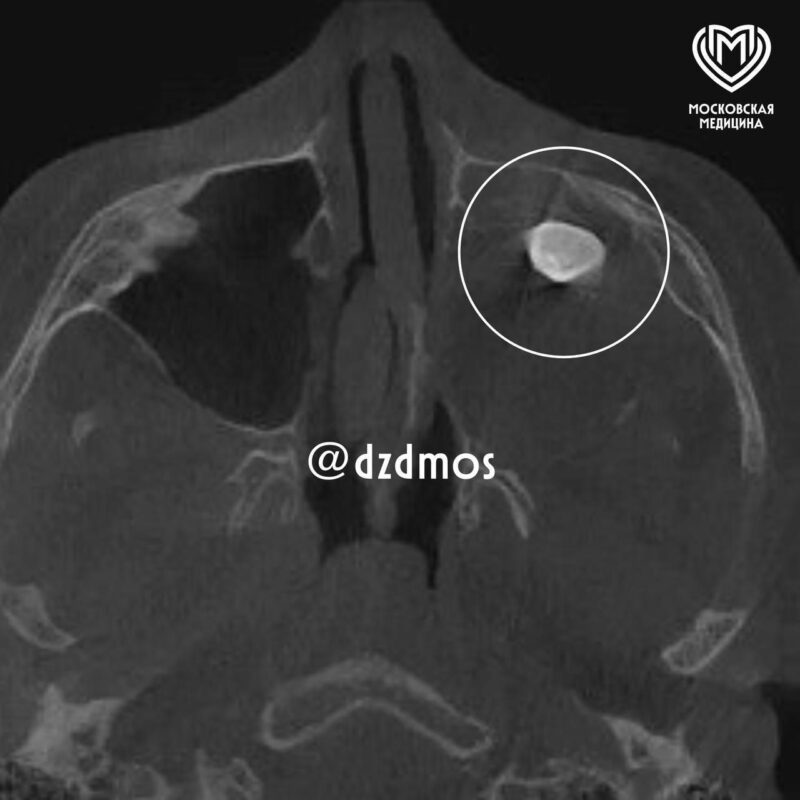

Все началось с визита в частную клинику. Там сделали снимок и обнаружили необычную причину — в гайморовой пазухе сформировался полноценный зуб. Врачи предложили удалить его через нос, но родители подростка решили не торопиться и обратились за вторым мнением, и, как позже выяснилось, это спасло парня от серьезных проблем.

Оказалось, что ни КТ, ни рентген раньше не показывали всей картины, потому что тератома занимала почти всю левую половину носа, «пряча» в себе зуб. Благодаря слаженной работе команды врачей опухоль удалось изъять целиком, единым блоком.